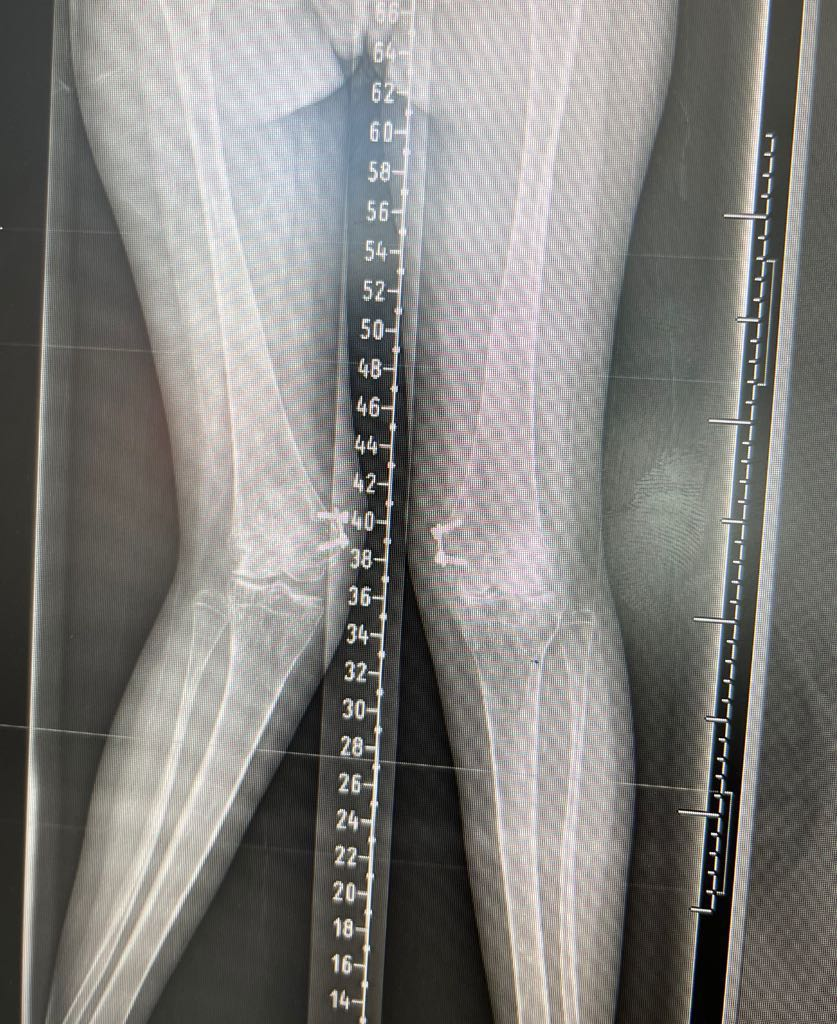

Mr Mughal is also highly experienced in deformity correction for both adolescents and adults, including knock knee, bow leg deformities and the complex condition known as miserable malalignment syndrome. He uses advanced computer based and 3D modelling techniques to plan personalised corrective surgery, aiming to preserve joints affected by early osteoarthritis. When combined with cartilage regeneration procedures, this approach enables him to offer a comprehensive and tailored treatment pathway.

Tibial osteotomy - (5-50)